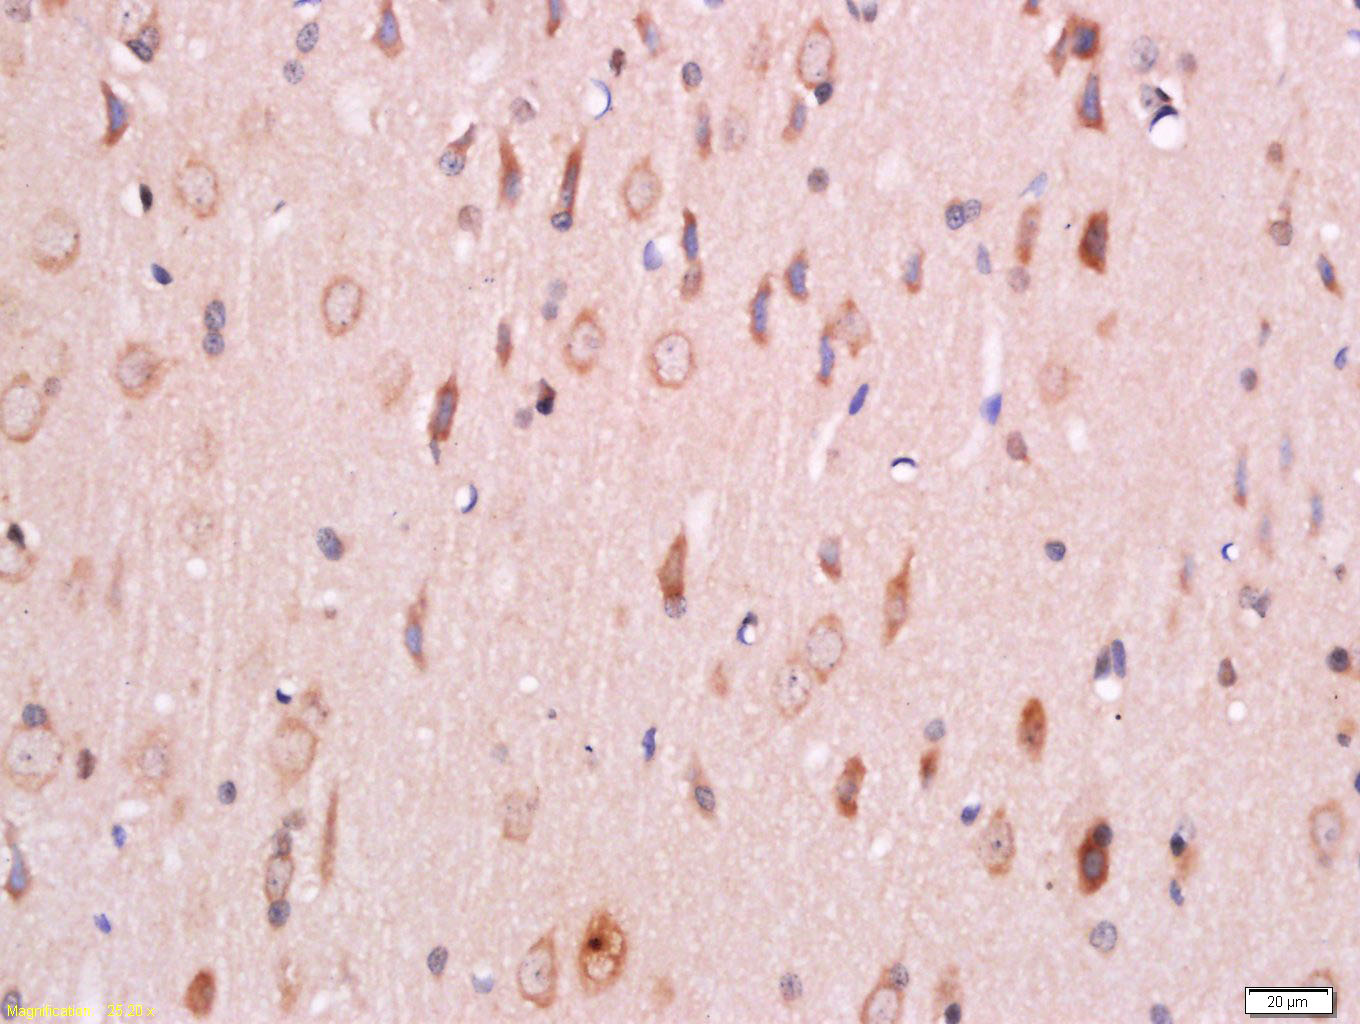

Tissue/cell: rat brain tissue; 4% Paraformaldehyde-fixed and paraffin-embedded; Antigen retrieval: citrate buffer ( 0.01M, pH 6.0 ), Boiling bathing for 15min; Block endogenous peroxidase by 3% Hydrogen peroxide for 30min; Blocking buffer (normal goat serum,C-0005) at 37℃ for 20 min; Incubation: Anti-PDK1 Polyclonal Antibody, Unconjugated(bs-3327R) 1:500, overnight at 4°C, followed by conjugation to the secondary antibody(SP-0023) and DAB(C-0010) staining